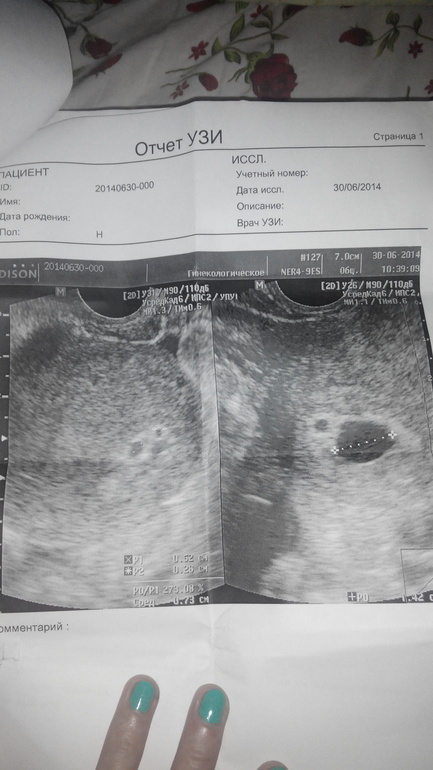

Анэмбриония почему

Анэмбриония почему 116 фотографий